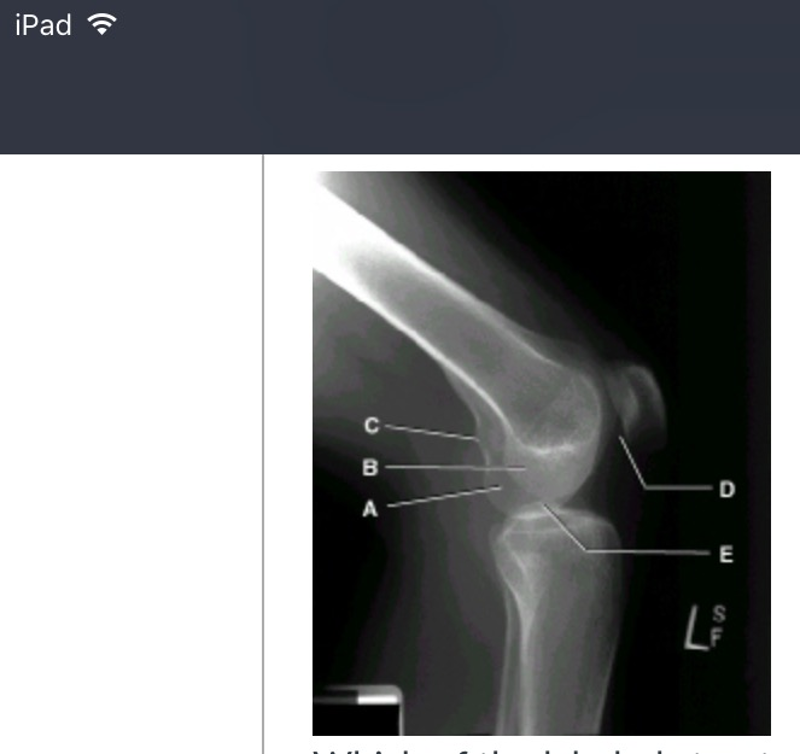

card image

(picture) which of the labeled structures is the lateral condyle?

b